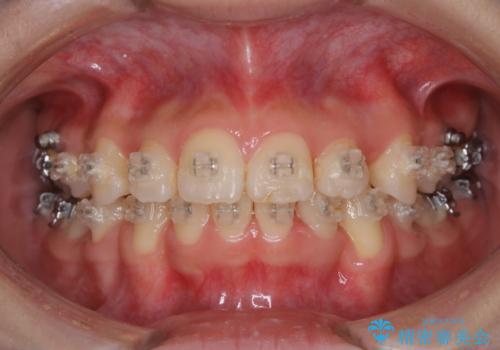

歯並が、がたついている場合はなおさら汚れが溜まりやすいです。矯正治療前や矯正中、定期的にPMTCをすることで、矯正治療中の歯肉トラブルを防ぐことにつながります。

- これから矯正治療を始めるため、今の状態でも歯をきれいにしておきたいとのことでした。PMTC60分コースを行いました。